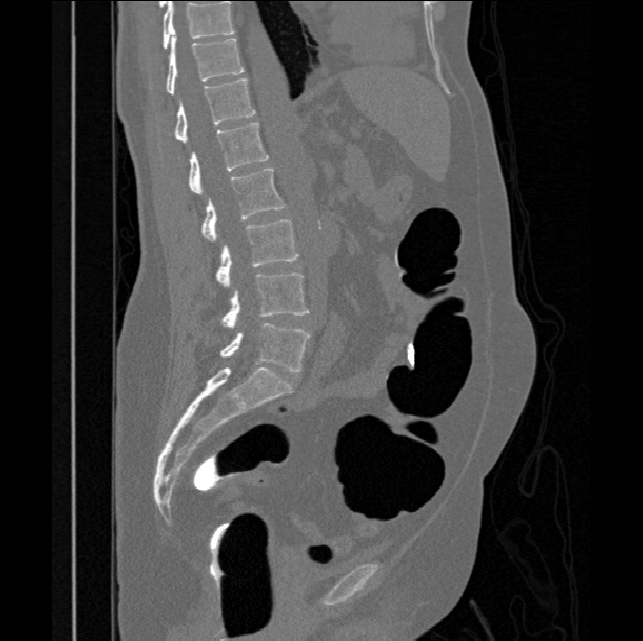

Spinal imaging via computed tomography (CT), magnetic resonance imaging (MRI), radiography, ultrasound, positron emission tomography (PET), and other radiologic imaging modalities is essential for noninvasively visualizing and assessing spinal pathology. Computational methods support and enhance a physician’s ability to utilize these imaging techniques for diagnosis, noninvasive treatment, and intervention in clinical practice. Analysis algorithms developed in the field of computer vision, computer graphics, signal processing, and machine learning have been adapted to analyze spinal images (Li et al., 2015). Conventionally, CT is preferred to study the spine due to a high bone-soft tissue contrast. There are diverse image appearance variations due to differences in vertebral position, metal artifacts and spinal diseases, etc., challenging the analysis algorithms. Fig. 1 gives some examples of these various conditions.

We calculate the two metrics of each vertebra, and the results are reported in Table 2. On the one hand, our experimental results are close to those reported in reference (Sekuboyina et al., 2020) with the same model (nnUnet), verifying the high quality of our annotations. On the other hand, Table 2 shows it is difficult to segment the diseased vertebrae (the DSC of L6 is almost 0). Specifically, the existence of L6 confuses the model, resulting in prediction dislocations (see the last row in Fig. 4). Thus, our labeled dataset, which contains many L6 cases, is very valuable for the diseased vertebrae segmentation (we have stated those cases that are hard for annotation in the readme.txt file). Table 2 illustrates that the model trained with our annotations can achieve good performance on our CTSpine1K dataset but a much worse performance on the VerSe Challenge datasets, which explains there is an obvious domain gap between our annotated dataset and the public dataset. We infer the reason is that the COlONOG dataset is based on an empty stomach and colon, confusing the deep learning model by the changes of air content in the abdomen (see Fig. 3). Therefore, our annotations are a good complement to the existing datasets.